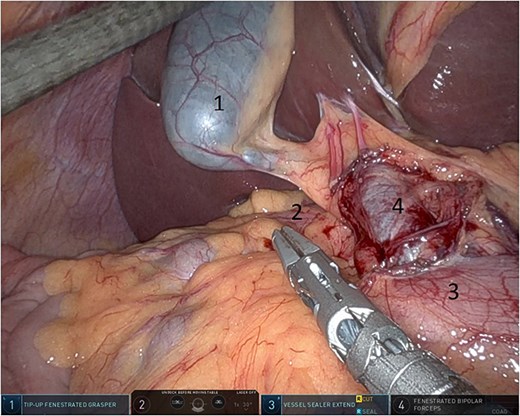

Upon entering the abdominal cavity, dilated bowel loops were observed (Fig. 2), and a significant portion of the colon was found herniated through the foramen of Winslow (Fig. 3). The herniated colon was covered by the pars flaccida (Fig. 4) (Video S1). Careful dissection was performed anterior to the hepatoduodenal ligament (Fig. 5). The gall bladder was retracted to the patient's right upper quadrant, which allowed for the retraction of the foramen of Winslow (Fig. 6) (Video S1). After carefully placing the tip of the instrument posterior to the portal vein and gently elevating it, the herniated colon was successfully reduced (Fig. 7) (Video S1).

Dissection anterior to the hepatoduodenal ligament (1: portal vein, 2: foramen of Winslow, 3:first part of the duodenum).